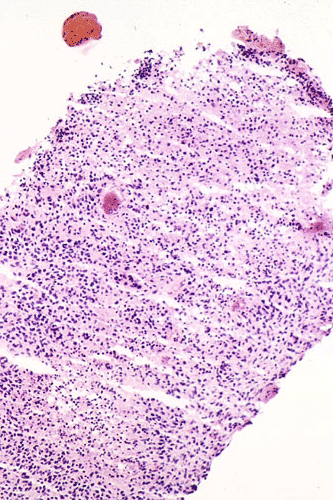

Intraoperative consultation: The cytologic preparation provides some very useful information. The cells form poorly defined clumps with elongated, pale pink cytoplasmic processes (Panel A, arrow). The nuclei are elongated, hyperchromatic and resemble "baking potato". Nucleoli are not seen  (Panel B), On the frozen section, a small streak of pale pink tissue suggestive of necrosis is present (Panel C and D). On high-magnification, the viable tumor cells have medium to large amount of cytoplasm and without distinct cytoplasmic border. They are densely packed, with hyperchromatic nuclei and does not form a specific pattern (Panel E). The interphase between the necrotic cells and the viable cells on frozen section is illustrated in (Panel F). The intraoperative diagnosis was "high-grade glial neoplasm with necrosis, probably glioblastoma".

Permenant section: The pathologic changes of the permenant sections are similar to that of frozen. Again, pseudopalisading necrosis is present (Panel G and H). Many of the nuclei are elongated and there is also considerable degree of pleomorphism.  Some of the cells have perinuclear clearing (Panel I). Positive staining for glial fibrillary acidic protein (GFAP) but not synaptophysin is demonstrated by immunohistochemistry. Although the perinuclear halo may suggestive anaplastic oligodendroglioma, the overall pathologic features, particularly the elongated nuclei and degree of pleomorphism, are that of a glioblastoma.

Glioblastoma has been known as glioblastoma multiforme for many years because of its diversity in histologic appearance.. The tumor cells can vary from relatively small cells to large, pleomorphic cells to multinucleated giant cells. There is significant variation between different histologic fields and different tumors. In general, most tumor cells retain some morphologic features of glial cells particularly astrocytes. Endothelial proliferation is found in most case. Necrosis can be extensive. Pseudopalisading necrosis is a common finding and refers to necrosis, often slit like and Y-shaped, that is surrounded by fusiform tumor cells arranging in a palisading fashion. Mitotic activity varies from moderate to brisk and atypical mitoses, more commonly found in tumor with large and anaplastic cells, can be present. As per the diagnostic criteria of the World Health Organization (WHO), the presence of anaplasia, increased mitotic activity, and endothelial proliferation with or without necrosis are required for the diagnosis of glioblastoma 1.